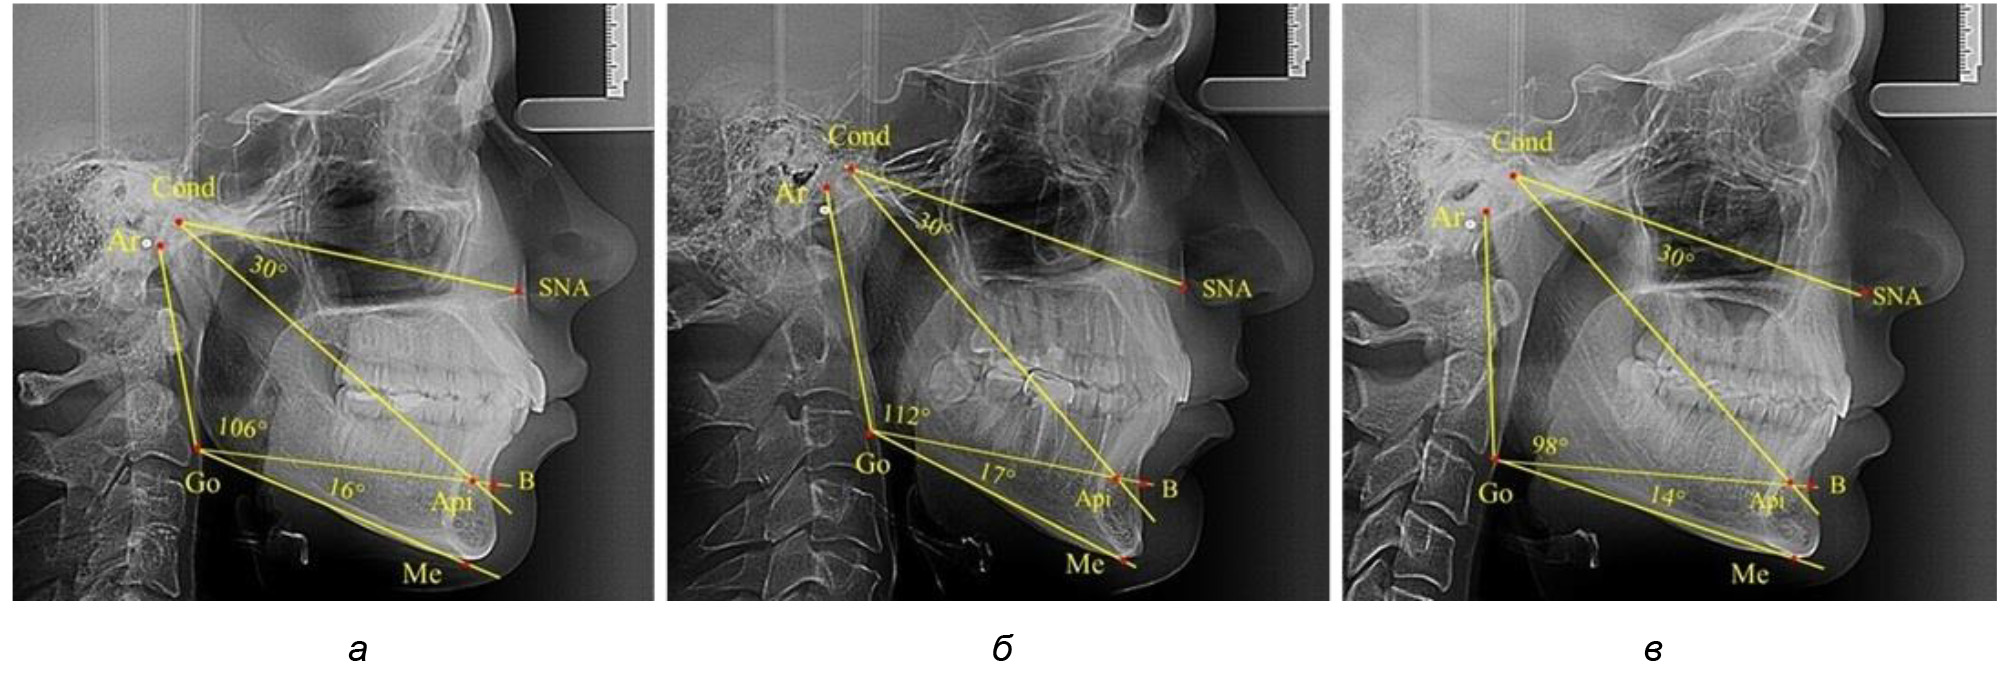

Для горизонтального типа роста было характерно достоверное р ˂ 0,05 уменьшение нижнечелюстного угла до (115,57 ± 0,56)°. Величина угла Ar-Go-Api составила (102,71 ± 1,62)°, а угол Api-Go-Me был (12,86 ± 0,74)° (рис. 3).

Рис. 3. Особенности ТРГ при нейтральном (а), вертикальном (б) и горизонтальном (в) типе угла нижней челюсти в постоянном прикусе

Таким образом, вне зависимости от величины нижнечелюстного угла, показатели угла гнатической части лица были в пределах 30°, что может расцениваться в качестве оптимального физиологического показателя параметров гнатической части лица. Анализ ТРГ проведен у 31 ребенка в различные периоды дентального онтогненеза, включая прикус молочных зубов и различные группы прорезывания постоянных зубов.

В то же время нижнечелюстной угол варьировал в широких пределах, в частности от 112 до 127°, и его средние значения при физиологическом прикусе составляли (120,57 ± 1,43)°. При этом составляющие части нижнечелюстного угла имели различия. Так, показатель угла Ar-Go-Api варьировал от 110 до 117°, при средних значениях – (107,12 ± 1,73)°. Величина угла Api-Go-Me составляла в среднем (13,56 ± 1,09)° при минимальных значениях 6° и максимальном показатели 19°. Анализируя параметры нижнечелюстного угла на телерентгенограммах с различными типами нижнечелюстного угла, выявлено, что у людей с нейтральными типами угла (в пределах от 119 до 123°) средний показатель был (121,83 ± 0,62)°. Величина угла Ar-Go-Api составила (107,89 ± 1,62)°, а угол Api-Go-Me был (13,83 ± 1,12)°.

При вертикальном типе нижнечелюстного угла его средние значения составили (125,51 ± 0,44)°, и достоверно отличалась от показателей людей с нейтральными значениями нижнечелюстного угла. Величина угла Ar-Go-Api составила (115,49 ± 2,14)°, а угол Api-Go-Me был (13,97 ± 1,26)°.